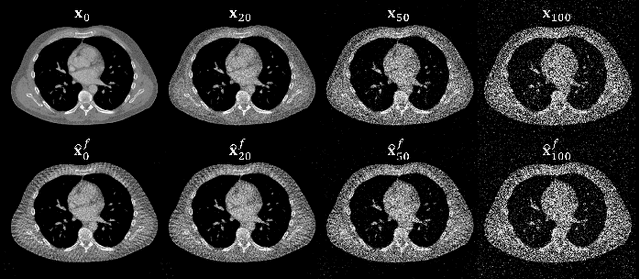

Abstract:Diffusion Posterior Sampling(DPS) methodology is a novel framework that permits nonlinear CT reconstruction by integrating a diffusion prior and an analytic physical system model, allowing for one-time training for different applications. However, baseline DPS can struggle with large variability, hallucinations, and slow reconstruction. This work introduces a number of strategies designed to enhance the stability and efficiency of DPS CT reconstruction. Specifically, jumpstart sampling allows one to skip many reverse time steps, significantly reducing the reconstruction time as well as the sampling variability. Additionally, the likelihood update is modified to simplify the Jacobian computation and improve data consistency more efficiently. Finally, a hyperparameter sweep is conducted to investigate the effects of parameter tuning and to optimize the overall reconstruction performance. Simulation studies demonstrated that the proposed DPS technique achieves up to 46.72% PSNR and 51.50% SSIM enhancement in a low-mAs setting, and an over 31.43% variability reduction in a sparse-view setting. Moreover, reconstruction time is sped up from >23.5 s/slice to <1.5 s/slice. In a physical data study, the proposed DPS exhibits robustness on an anthropomorphic phantom reconstruction which does not strictly follow the prior distribution. Quantitative analysis demonstrates that the proposed DPS can accommodate various dose levels and number of views. With 10% dose, only a 5.60% and 4.84% reduction of PSNR and SSIM was observed for the proposed approach. Both simulation and phantom studies demonstrate that the proposed method can significantly improve reconstruction accuracy and reduce computational costs, greatly enhancing the practicality of DPS CT reconstruction.